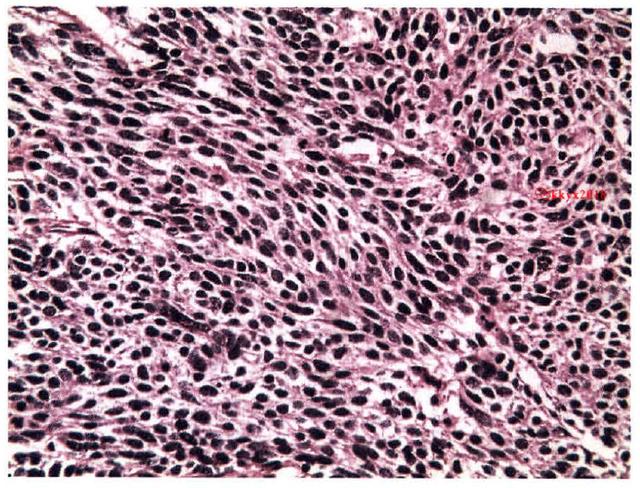

肺腺癌:癌细胞沿肺泡壁呈多层生长,形似腺样结构,有乳头形成,肺泡间隔